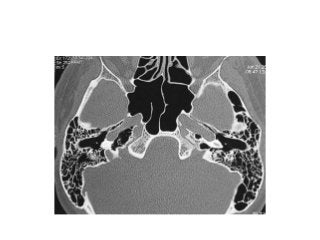

Temporal bone CT. Look at the sub-cochlear canaliculus or sub-cochlear

tunnel that can allow endoscopic transcanal retrocochlear access to the IAC

and drain the petrous apex cells